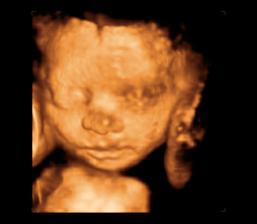

26 tt../1.4.2009/ naša paulínka je stráášne zlatá, boli sme si pozrieť na 4D utz. ..tvárila sa veľmi dôležito, až nafúkano...hehe..vôbec sa nechcela usmievať... nakoniec sa nám aj zasmiala...v brušku veľmi vyvádza, maminke dosť vytláča všetky časti telíčka, čo je niekedy aj dosť bolestivé...ale vydržíme, drobečkovi je tam určite tiež pritesno..a ešte aj stále viac a viac bude... strááášne sa na ňu tešíme🙂))